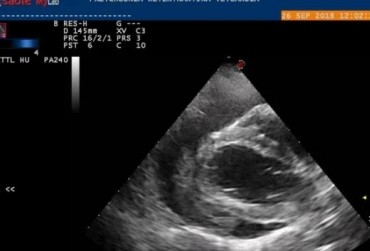

Obraz echo serca przez zabiegiem usunięcia worka osierdziowego 3

19 lutego 2019

Rafał Kraszewski